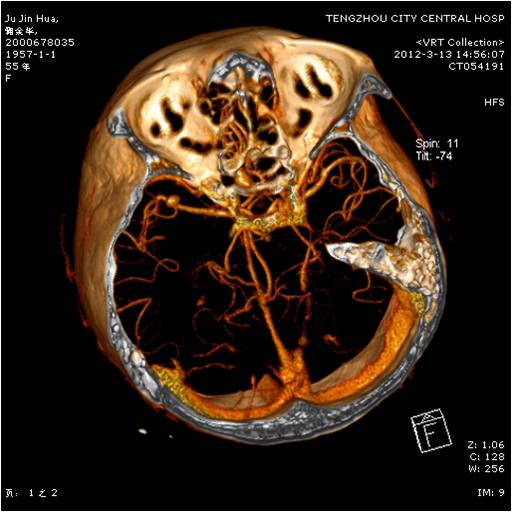

動(dòng)脈瘤夾閉術(shù)前 動(dòng)脈瘤夾閉術(shù)后

垂體瘤術(shù)前 垂體瘤術(shù)后